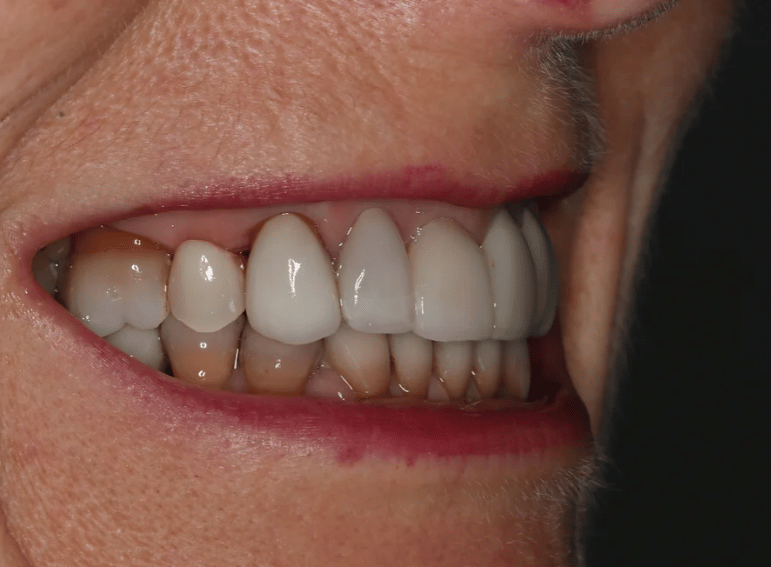

Case 3 – Implants

Removal of a premolar and replacement with an implant.